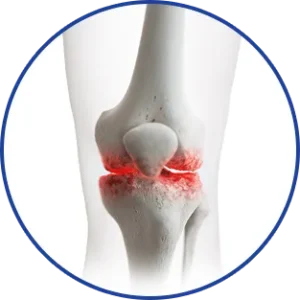

La douleur articulaire ou musculaire rend-elle même les gestes les plus simples difficiles, voire impossibles ?

Vivre avec la douleur est un combat quotidien

Articulations raides

Mobilité réduite

Douleurs constantes

Solution de refroidissement instantané pour les douleurs articulaires et musculaires

ACTION CIBLÉE: Réduit l’inflammation et la raideur exactement là où vous en avez besoin.

Ignorer les douleurs articulaires et musculaires ne les fera pas disparaître — cela pourrait même aggraver la situation.

Avec le temps, la douleur non traitée peut entraîner:

Aggravation des symptômes

La raideur et l’inconfort peuvent s’intensifier, rendant les mouvements plus difficiles.